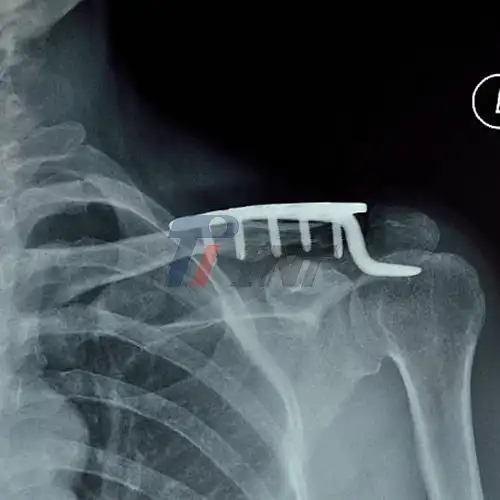

2025-06-18 10:40:13Reliable Titanium Plates for Collar Bone Injuries in Trauma Hospitals

2025-08-19 09:50:53Titanium vs. Other Materials: What's Best for Your Collar Bone?